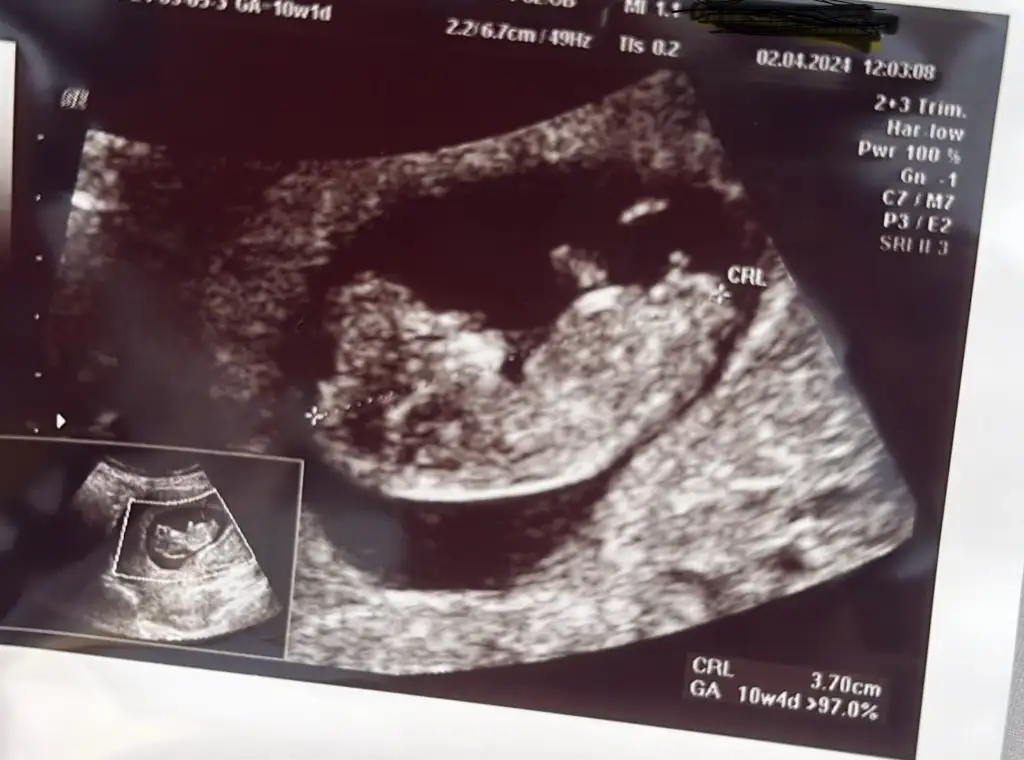

Kızlar merhabalar bende bugün kontrole gittim 10+1 Suan cinsiyet için tabiki erken dedi çıkıntı gördü fakat net olarak ay sonu kontrolde söyleyebilirim dedi sizlerin tahminini merak ettim anlayan var mıdır ?

• EC99E576-8B70-4DFB-8980-B5013BCC9D40.webp

33,8 KB · Görüntüleme: 70

Hayırlı olsun maşallah Kafa yapısından erkek gibi gördüm ben